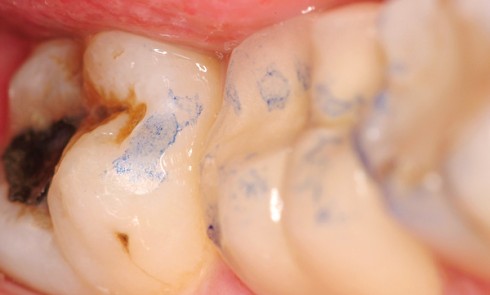

L’usure dentaire est de plus en plus fréquente au sein de nos cabinets. Nos patients y sont sujets de par...

Article réservé à nos abonnés La « préparation initiale occlusale » en prothèse fixée

Il est essentiel d’évaluer la capacité de la restauration d’une dent délabrée à remplir les fonctions auxquelles cette dent était...